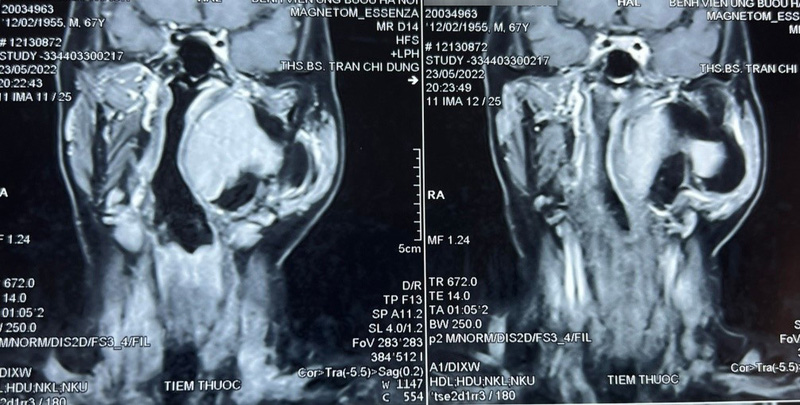

Qua thăm khám và đánh giá, bác sĩ phát hiện một khối u lớn vùng cổ kích thước khoảng 10×8 cm, thuộc khoảng bên họng, trải dài từ nền sọ xuống hạ họng, đẩy lệch thành bên họng vào trong, gồm 2 phần: phần nông nằm dưới tuyến mang tai và phần còn lại nằm sâu hơn. Chẩn đoán sơ bộ ban đầu khối u là lành tính, ranh giới không rõ ràng.

Thông qua hội chẩn, các bác sĩ quyết định tiến hành phẫu thuật sớm lấy bỏ khối u tránh nguy cơ khối u chèn ép vào đường thở, đường ăn, thần kinh, mạch máu và các thành phần liên quan khác. Tiên lượng cuộc mổ là rất khó khăn, đường tiếp cận chính là qua mổ mở từ vùng cổ, phải thực hiện các thao tác phẫu thuật trong không gian hẹp, có thể kết hợp thêm hỗ trợ nội soi.

Theo bác sĩ Trần Chí Dũng, Khoa Ngoại Đầu cổ, khoảng bên họng là khoang giải phẫu kéo dài từ nền sọ tới vùng họng miệng. U khoảng bên họng là loại ít gặp trong vùng đầu cổ, chiếm khoảng 1%. Tỉ lệ u lành chiếm chủ yếu (70 – 80%), còn lại (20 – 30%) là u ác tính. Dù là u lành hay ác tính thì phương pháp điều trị chính đều là phẫu thuật.

Do đặc điểm giải phẫu phức tạp, nằm trong vùng cổ sâu, liên quan hầu hết thần kinh, mạch máu lớn và các thành phần quan trọng khác của đầu cổ, phẫu thuật u vùng khoảng bên họng luôn là loại khó khăn bậc nhất trong chuyên khoa phẫu thuật đầu cổ.